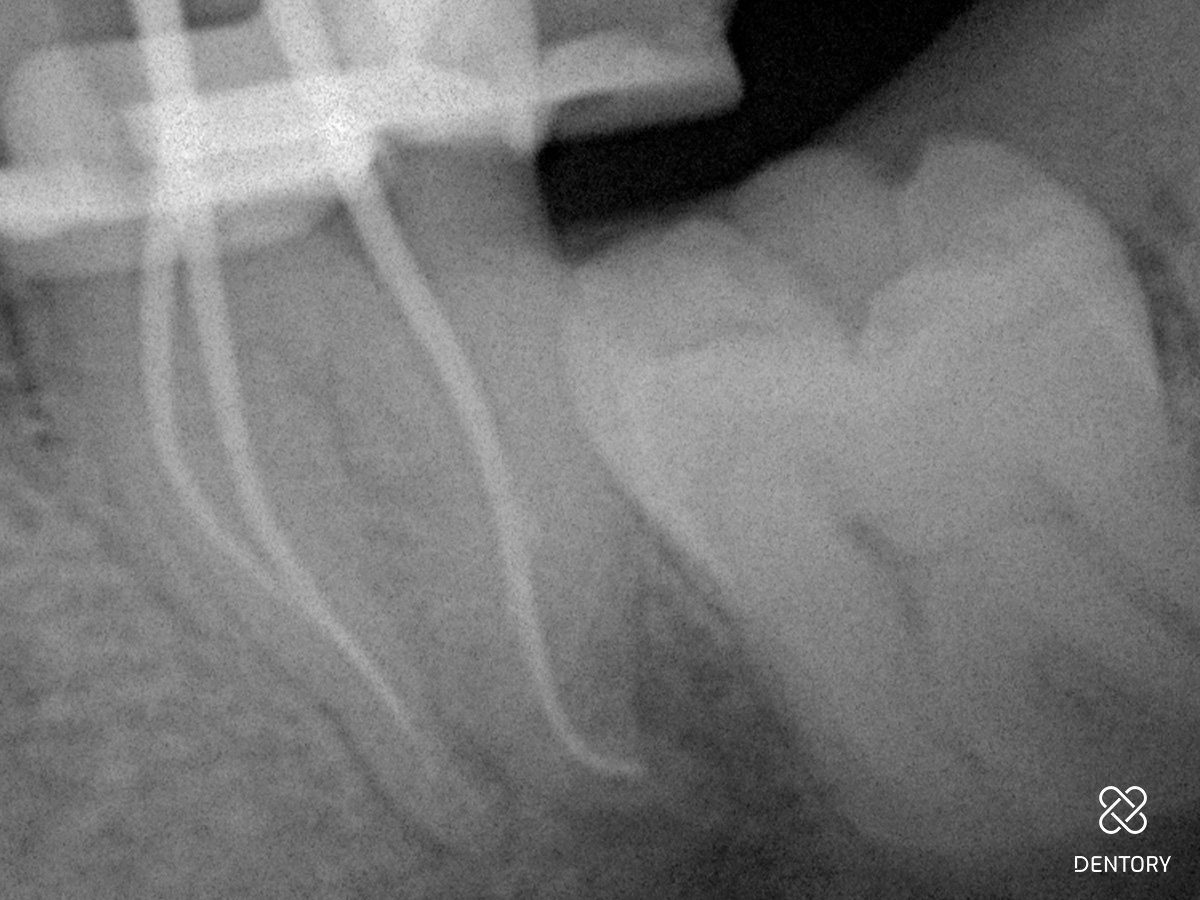

Abbildung 1

Diagnoseaufnahme (alio loco) Regio 37: Symptomatische apikale Parodontitis (PAI 4). Als Besonderheit erkennt man bereits die S-förmige Kanalkrümmung in der mesialen Wurzel und die J-förmige apikale Krümmung im distalen Kanal.

Abbildung 2

Röntgen-Messaufnahme: Aufgrund der Kanalkrümmung erfolgte die Messaufnahme bereits nach der Erstellung eines Gleitpfades bis ISO 10. Der mb und ml Kanal verfügen jeweils über ein separates Foramen.